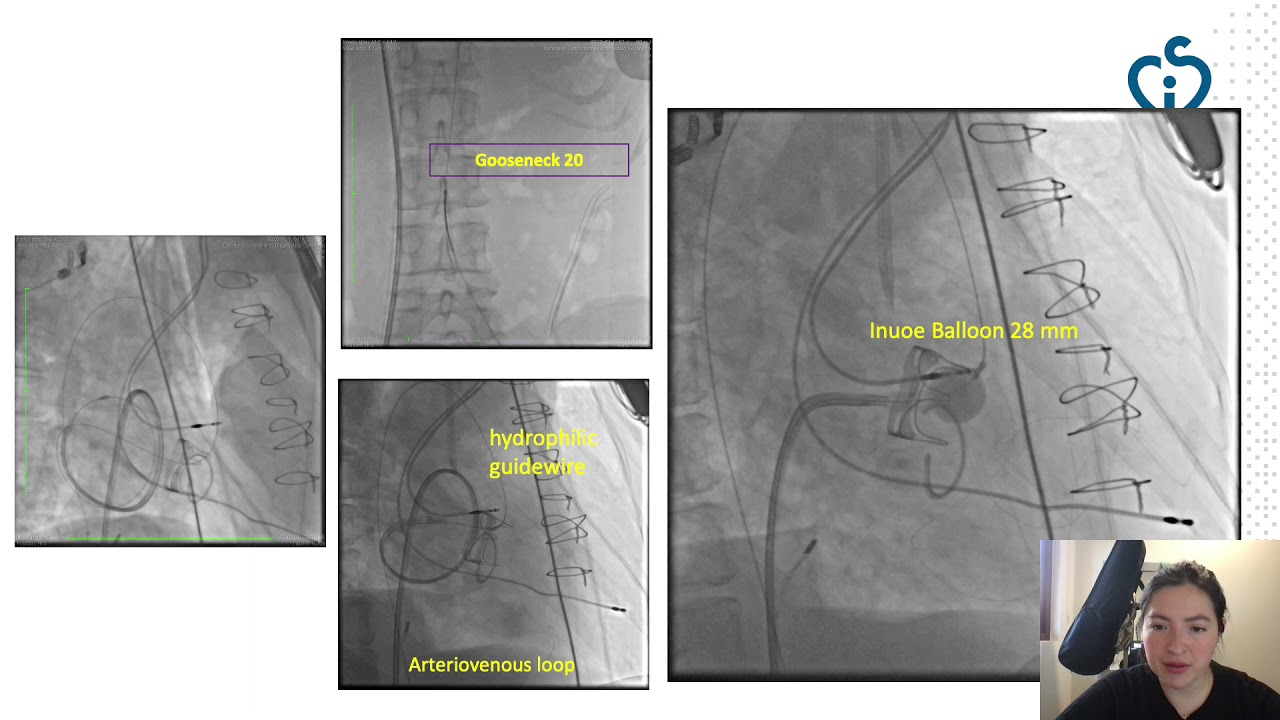

Management of embolised stent to the distal aortic arch

By: Diogo Faim, Centro Hospitalar Universitário de Coimbra, Coimbra, Portugal